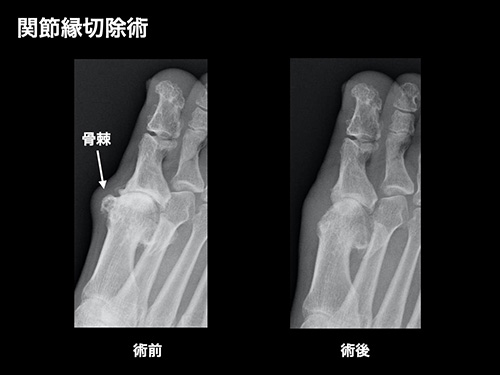

関節縁切除術

母趾の変形した関節周囲の骨棘を切除して動きを改善します。

母趾の付け根の関節は通常でも伸展時(ゆびを反らす時)に大きなストレスがかかっています。強剛母趾になると軟骨がすり減り、関節の隙間がせまくなります。また関節周囲に骨のとげ(骨棘)ができるために動きが悪くなり痛みが生じます。